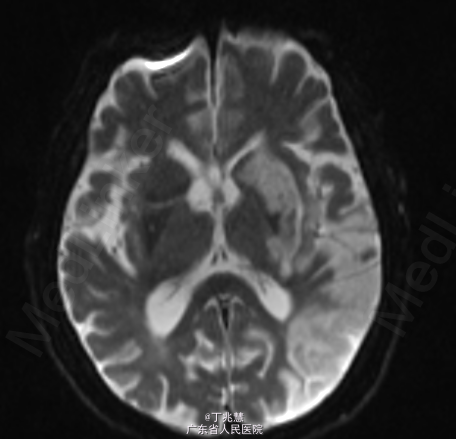

女性,46岁。因“反复发热、头痛2月”入院。患者自2个月前无明显诱因出现头痛,呈持续性,起病初期头痛程度轻,可忍受,自服药治疗(具体用药不详)病情未见好转,且头痛程度逐步加重,难以忍受,无恶心,呕吐,无肢体抽搐,间中有发热,体温最高可达39.2摄氏度。 既往糖尿病史5年,控制不佳。

查体:心肺腹查体未见异常。神经专科:右侧上下肢肌力0级左侧上下肢体肌力5级。 颈强直,颏胸距4横指,双侧Kernig征(+)。

诊断:结核性脑膜脑炎; 治疗:抗结核治疗。

随访:患者转胸科医院进一步治疗,具体不详; 讨论:结核菌一般侵犯脑膜多见,较少累及大脑实质,本例患者累及脑实质,有肢体无力表现。经规律抗结核治疗后预后相对良好。